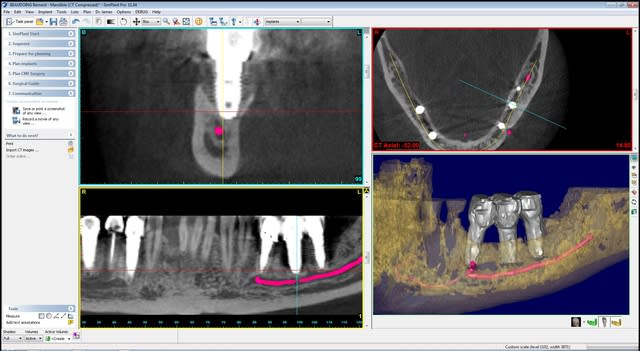

quelques images en 3 D...

Bernard cross section apfhj5 - Eugenol

Bernard cross section  2  ctt7jw - Eugenol

Bernard overview edbft1 - Eugenol

Bernard overview  2  nlgyly - Eugenol

Bernard panoramic l8hei0 - Eugenol